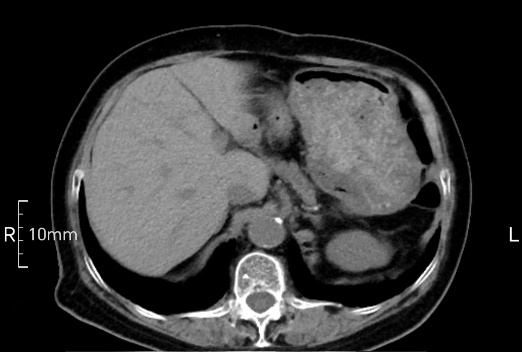

看看下面三幅便知遵醫(yī)囑的重要性。

完美禁食且喝飽飽,胃壁完美展現(xiàn)。

CT檢查前的“禁食”和“喝飽”,看似矛盾,實則合情合理,分工合作:空腹:是為了讓上腹部(肝膽胰脾腎等)的圖像清晰無干擾,并保障檢查安全。喝水:有效的充盈胃部和、腸道使圖像清晰呈現(xiàn)。兩者巧妙配合,都是為了給您一個最精準的診斷結(jié)果。